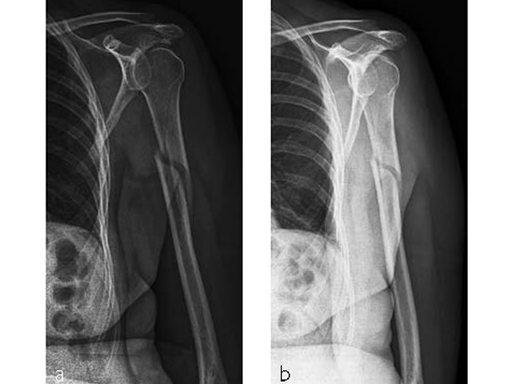

Case 1: AO 12C1 fracture following fall (Case provided by Stefaan Nijs, Leuven, Belgium)

A 54-year-old woman, and otherwise healthy patient, fell during her holidays and sustained an AO 12C1 fracture (Fig 1). There was no major soft tissue trauma. Other lesions: avulsion at the 5th metatarsal base, and concussion.

Surgery took place on day 9 after the accident. The patient left the hospital the day after surgery.